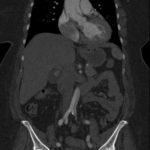

Because aortic dissection was suspected, the patient underwent urgent computed tomography (CT) angiogram of her chest, abdomen and pelvis that revealed her diagnosis.

The patient was found to have a Stanford type A dissection (see yellow arrow) with visible false lumen starting at aortic arch (see green circle). The dissection extended into the descending aorta (see blue circle) as shown by the false lumen (red highlighted area) visible on CT. The radiologist performed a reconstruction of the aorta, which showed that the left kidney was not being perfused, making the kidney not visible on the reconstruction.

In this case, the patient improved, but repeat imaging revealed 50% of her left kidney was no longer functional. However, the patient remained in stable condition and had no residual neurological deficits.